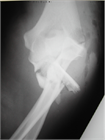

1. 直達外力による肘頭骨折と上腕三頭筋の牽引力によって起こる肘頭剝離骨折がある。

前者に対しては観血整復内固定術が行われることが多く、tension band wiring、intramedullary screw fixation、肘頭用アナトミカルロッキングプレートによるプレート骨接合術などの選択肢がある。